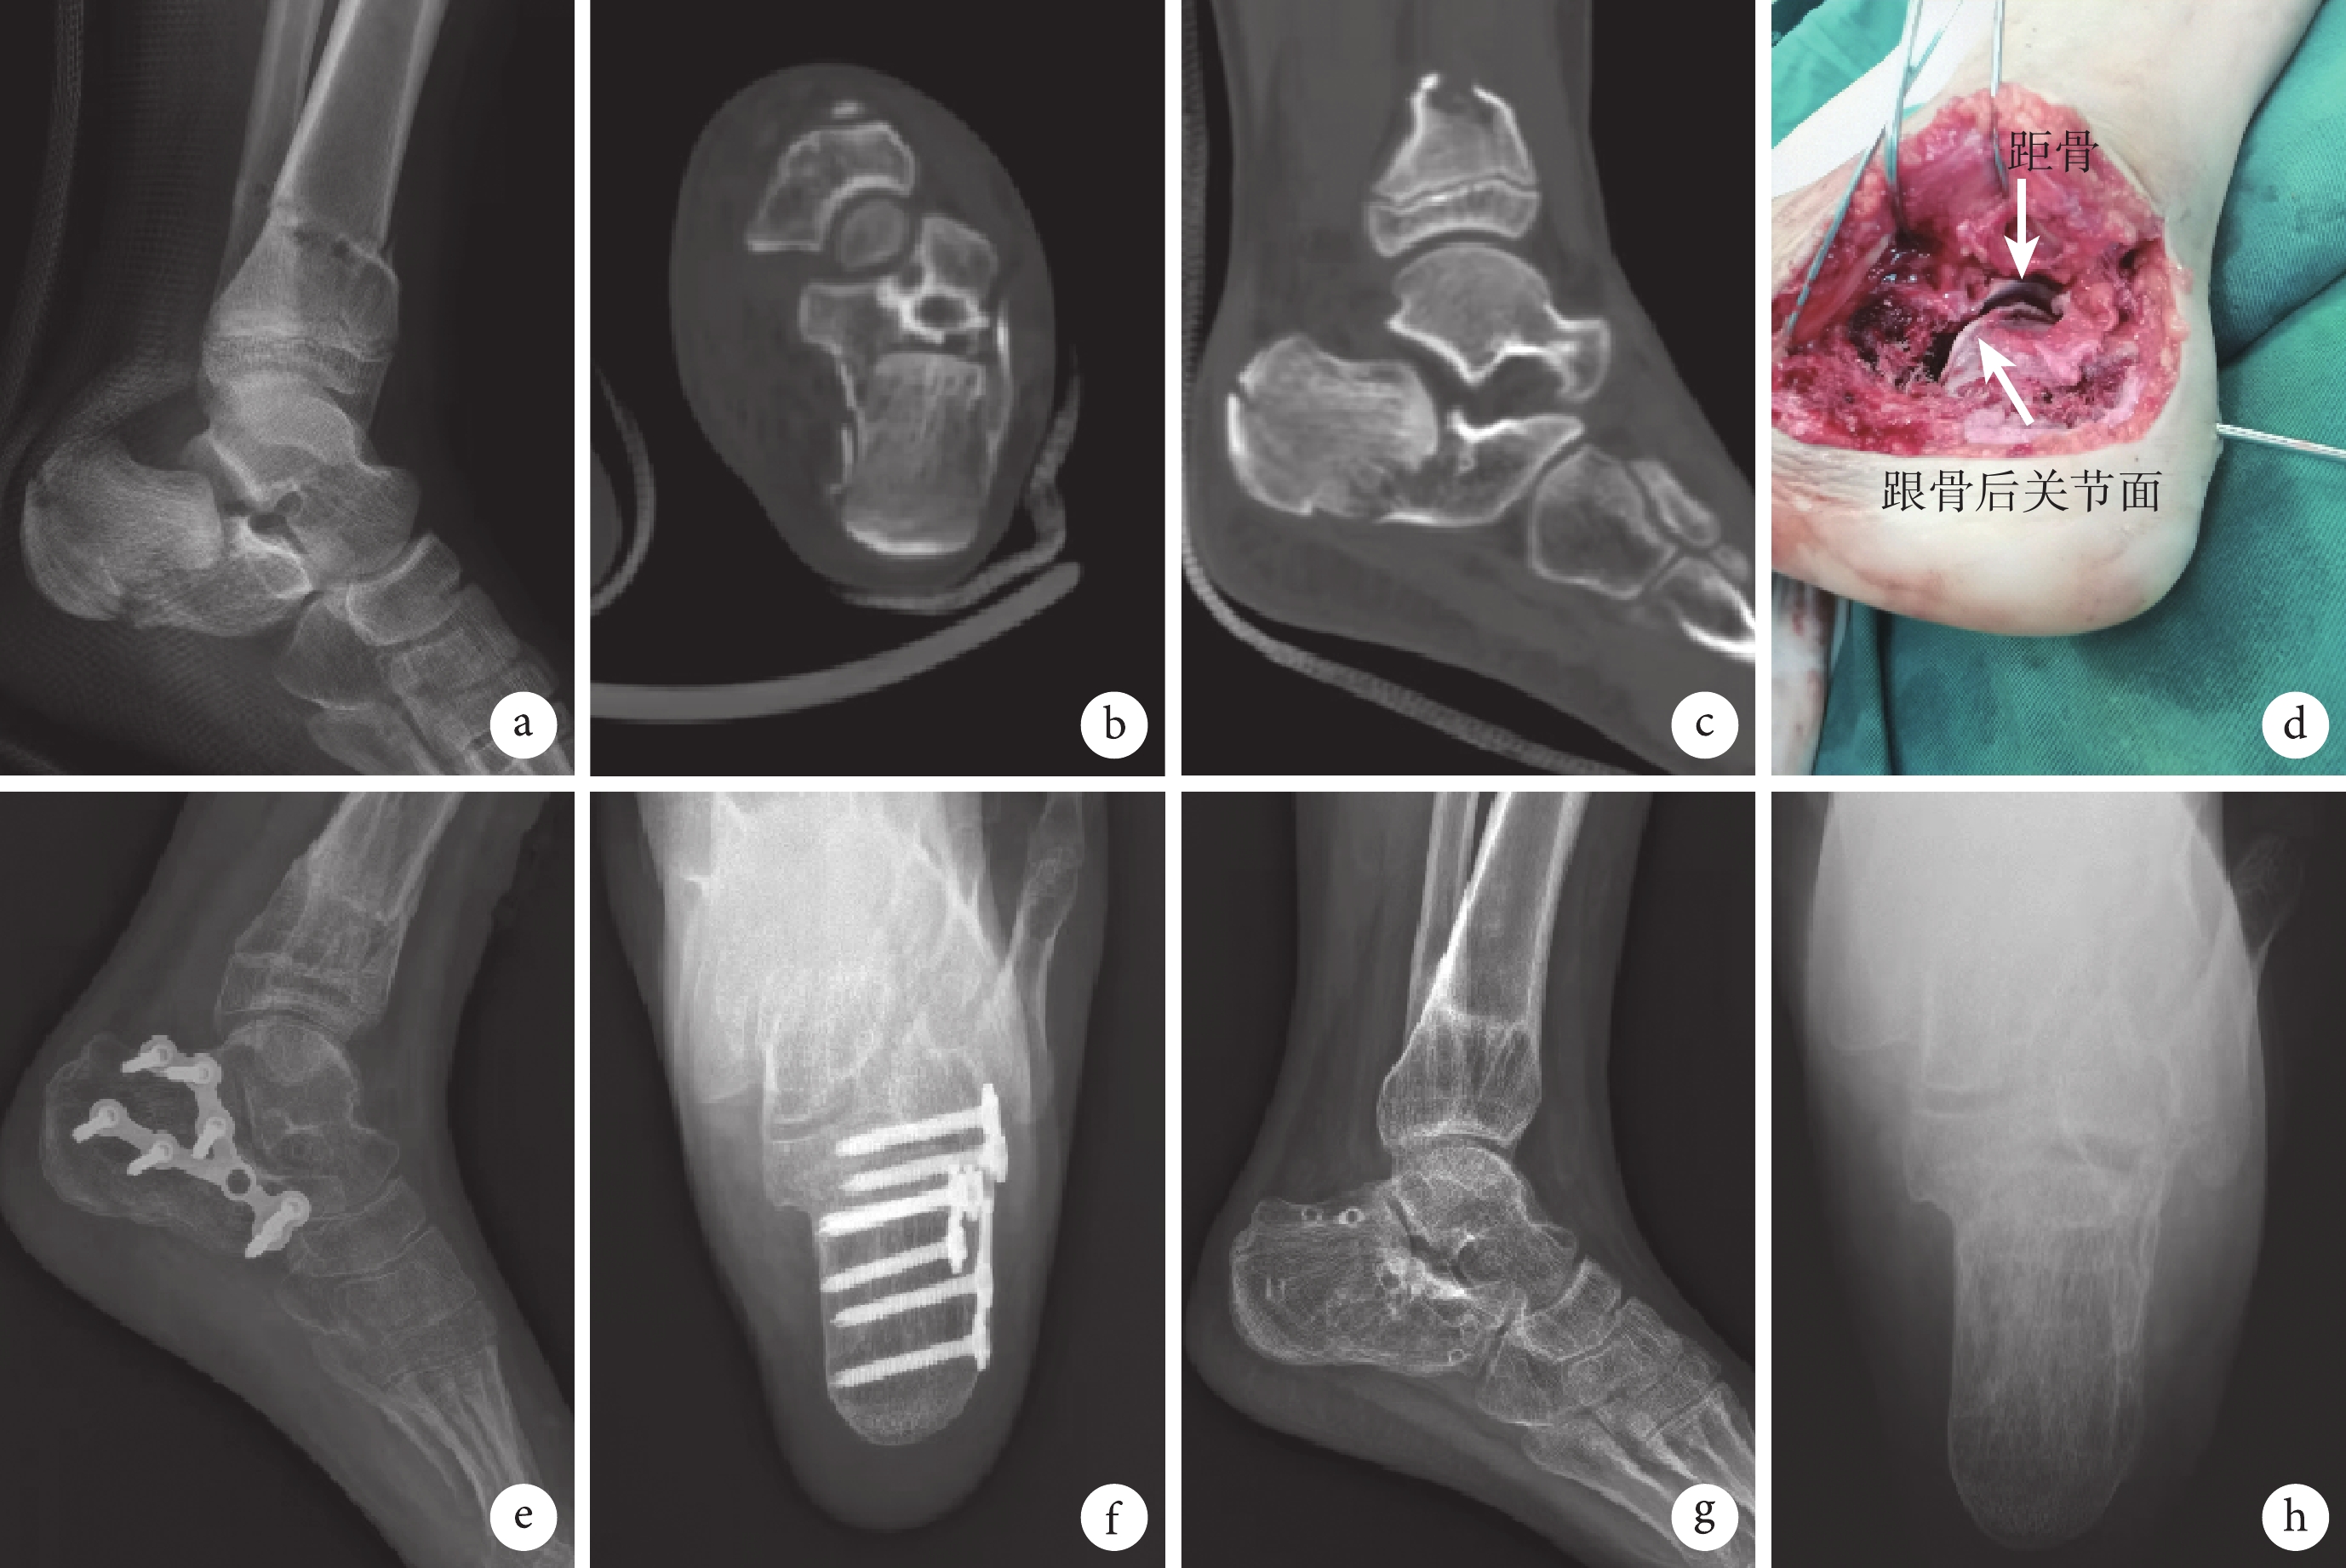

a~c. 術前側位X線片以及CT示左側跟骨骨折,后關節面塌陷;d. 術后1個月側位X線片示Gissane角及Böhler角恢復正常,骨痂形成;e、f. 術后14個月側位及軸位X線片示Gissane角、Böhler角無丟失

Figure2. A 12-year-old boy in the K-wire group with intra-articular fracture of the left calcaneus (Sanders type Ⅱ)a-c. Preoperative lateral X-ray film and CT showed the left calcaneal fracture and the posterior articular surface collapse; d. Lateral X-ray film at 1 month after operation showed that the Gissane angle and Böhler angle returned to normal, and callus formed; e, f. Lateral and axial X-ray films at 14 months after operation showed that the Gissane angle and Böhler angle were normal

術后鋼板組1足發生切口皮膚壞死,經封閉式負壓引流、換藥后愈合;其余患兒切口均Ⅰ期愈合。兩組患兒均獲隨訪,隨訪時間12~39個月,平均19個月。X線片復查示兩組骨折均愈合,無延遲愈合;鋼板組愈合時間為(2.65±0.71)個月,克氏針組為(2.24±1.38)個月,差異無統計學意義(t=1.161,P=0.253)。X線片復查示,末次隨訪時跟骨Gissane角、B?hler角均恢復正常,組內手術前后比較差異均有統計學意義(P<0.05),組間手術前后差值比較差異無統計學意義(P>0.05),見表1。鋼板組于術后11~22個月,平均16.8個月取出鋼板。見圖1、2。